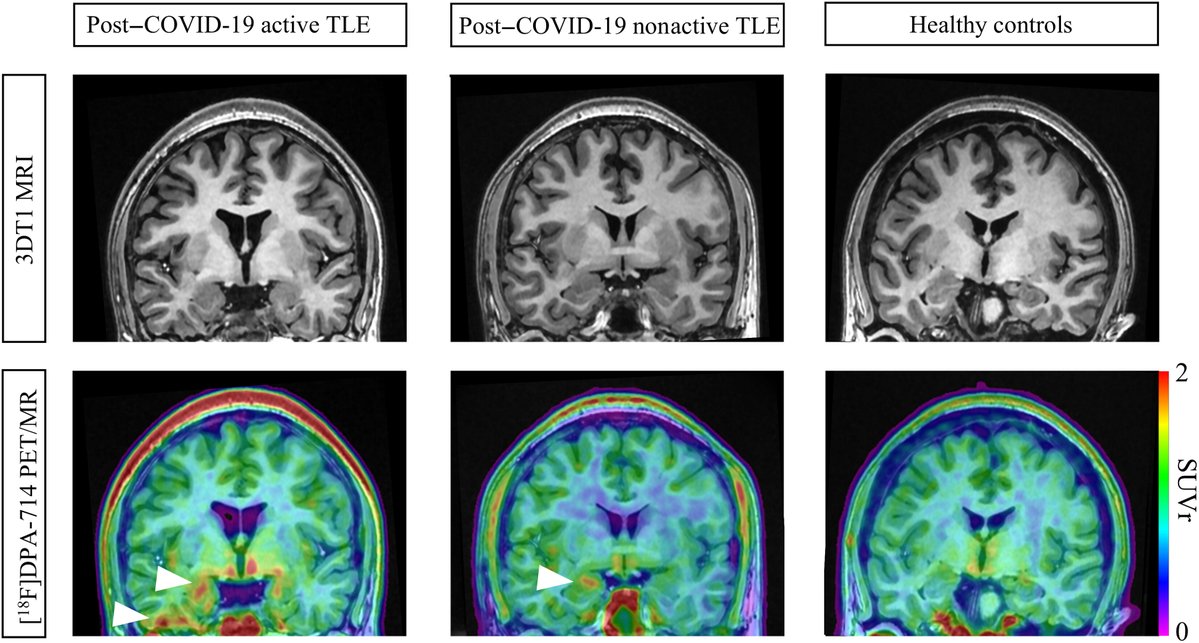

Neuroinflammation correlates with worsened epilepsy after COVID-19 infection, according to a new @ScienceAdvances study. https://t.co/SjrvZXkyP5